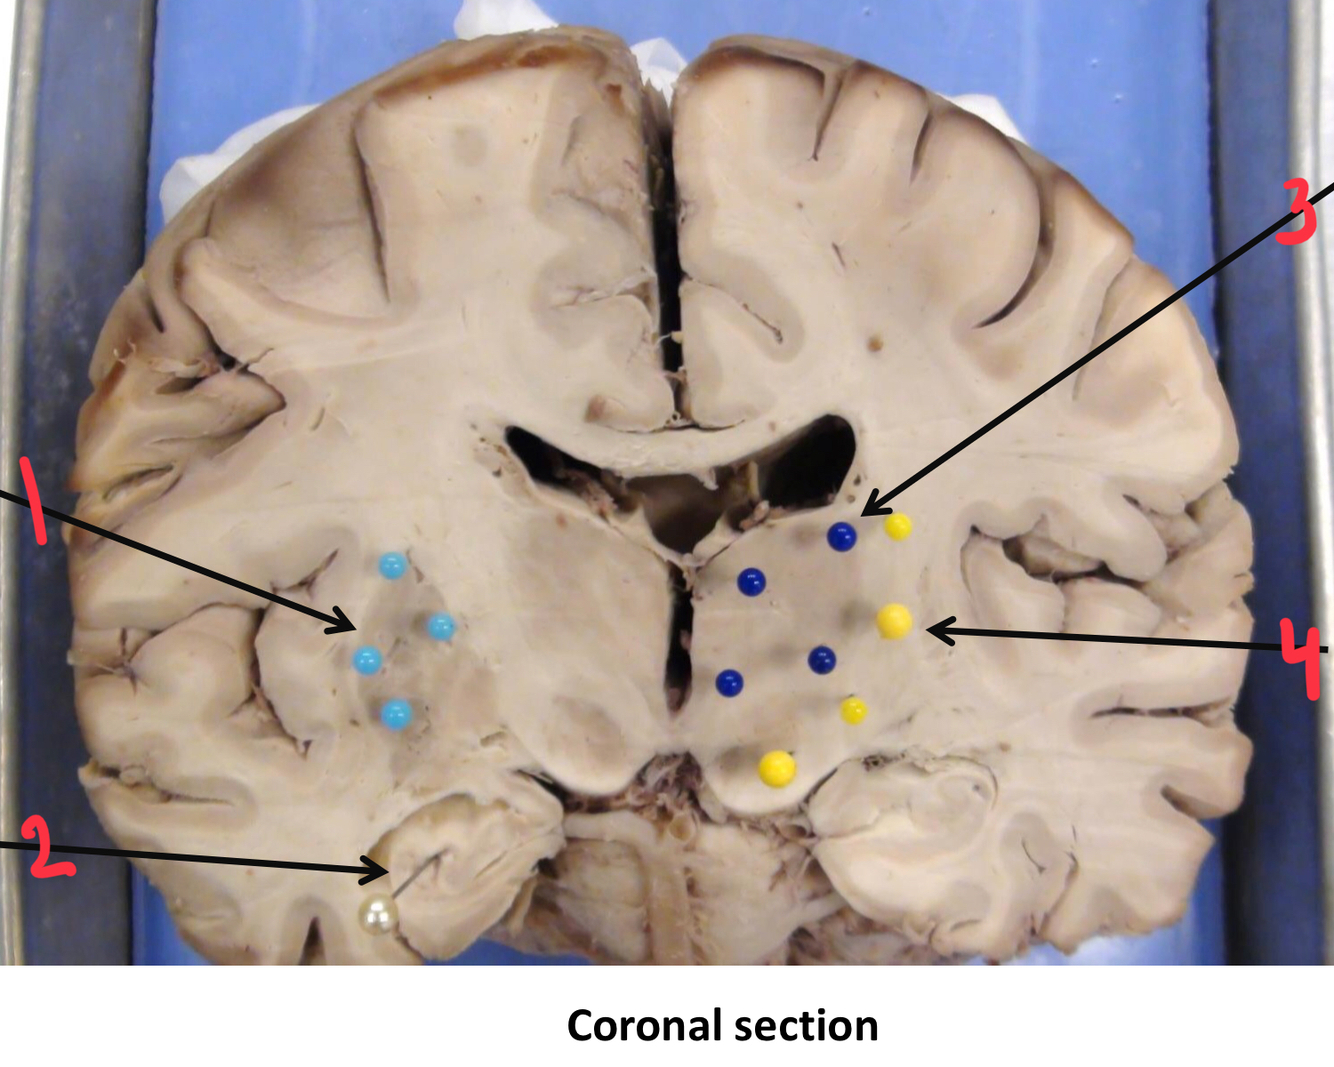

1

putamen

2

hippocampus

3

thalamus

4

internal capsule